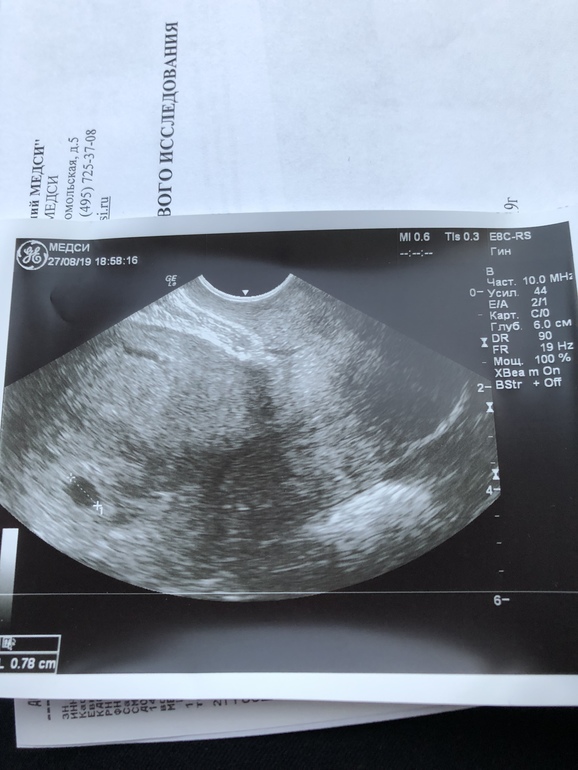

Девочки,подскажите,может ли быть все хорошо? Пошла на узи,врач назначила для подтверждения маточной беременности. Хгч сдаю регулярно,рост нормальный. Сегодня 23 ДПО или 10дз. Это моя первая в жизни и очень долгожданная беременность,очень переживаю. НА узи нашли только плодное яйцо д9мм,про жм и тем более эмбрион ничего не сказали,врач какой-то вялый,я спрашиваю все хорошо,он ну поменьше ,типо маленький срок. спросил про хгч,сказал, ну это нормальный рост. Типо развивающуюся пока поставить не могу,просто беременность малого срока. Приходи мол через 2 недели.(оборудование должно быть хорошее,делала в ЦИРе)

Не было ничего на 5 неделе, фото скинула вам. Только плодное яйцо. Срок маленький ещё не видно ничего. Не надо переживать, это вредно

Это узи на 5 неделе, а следующее уже в 7 недель.